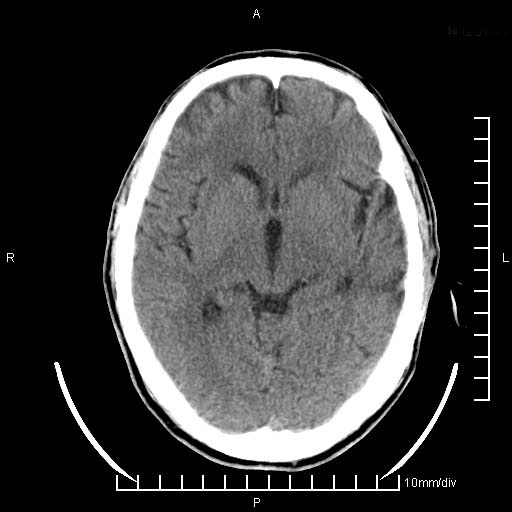

临床以双下肢浮肿,疼痛收治,无明显神经系统症状,既往无梗塞,出血病史。左颞叶见低密度灶,考虑什么?

考虑左侧颞叶脑软化灶。

无强化 无占位 软化灶吧

无强化、 无占位、局部脑沟增宽, 软化灶吧。